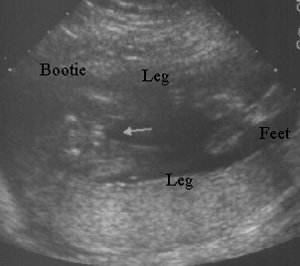

الولد

ولد في الأسبوع ال 15

ولد في الاسبوع ال16

الأسبوع ال17

الأسبوع ال18